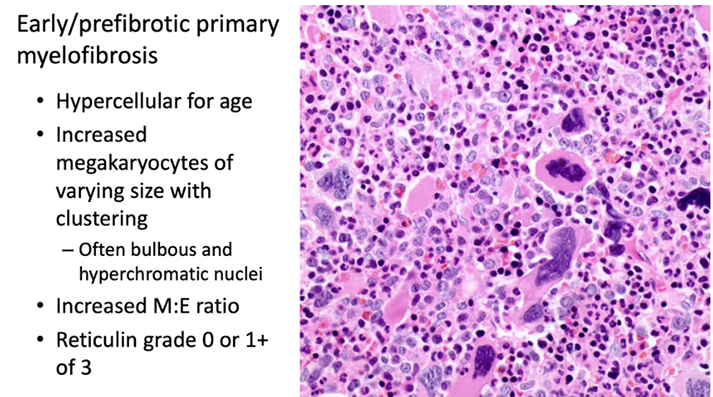

Challenges of diagnosis PMF[2]:

- in early phases of disease, fibrosis is minimal or absent

- correct diagnosis is important, since early PMF has a high risk of progression to a fibrotic disease phase and has worse prognosis than other MPNs

-- increased bone marrow cellularity and more frequent, clustered megakaryocytes in early PMF compared to ET

1.) Mkc prolif + atypia, c fibrosis (if no fibrosis, then need hypercellular BM)